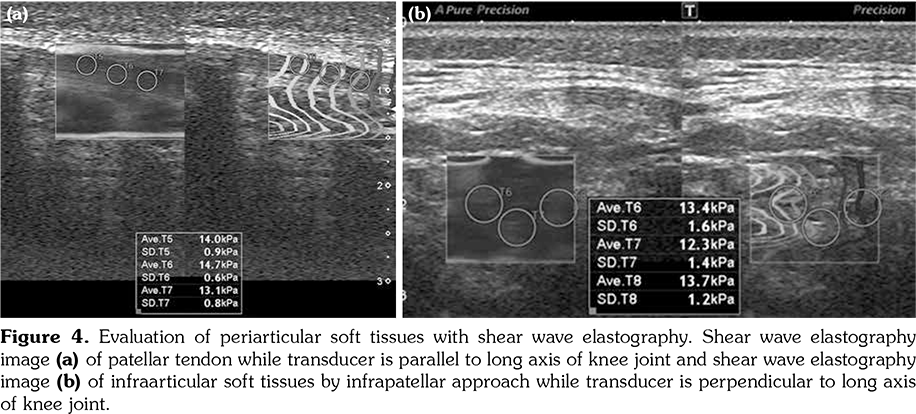

All patients and healthy volunteers were screened with Canon Aplio 500 Platinum US device (Canon Medical Systems, Tokyo, Japan) equipped with SMI, PD and SWE functions. All participants were examined in supine position and their knees were in extension (Figures 1, 2). Once the gray scale US examination confirmed the arthritis based on synovial thickening, joint effusion and periarticular echogenicity, then SMI and SWE were performed to the supraarticular and infraarticular soft tissues concerning the synovium and periarticular soft tissues. VI is a novel parameter determined for SMI and PD corresponding the ratio of colored pixels to the total pixels within the selected region of interest (ROI). VI was calculated automatically on colored SMI and PD images over the selected rectangular shaped ROI with edges measured 5x15 mm (Figure 3). Mean VI values were calculated by averaging results of three different acquisitions of PD and SMI. The ROI was placed perpendicular to the long axis of the knee joint at the supraarticular and infraarticular locations including the synovium and periarticular soft tissues. On SWE evaluation, the QT and PT were demonstrated along with their long axis. Three different ROIs for SWE were performed from the tendon halves closer to the knee joints. Each ROI was in circle shape and 3 mm in diameter. We depicted mean elasticity for PT, QT, supraarticular soft tissues (SAST) and infraarticular soft tissues (IAST) (Figures 4, 5).

No statistically significant difference was found between the mean ages of study and control subjects. Mean VI values in the study group obtained from SAST including synovium and suprapatellar fat pad were 8.2±3.4% for SMI and 9.1±3.1% for PD. Those were found as 2.9±1.4% for SMI and 3.4±1.4% for PD in the control group. When the study and control groups were compared, there was a statistically significant difference between VI values determined by SMI (p<0.001) and PD (p<0.002), respectively. In the study group, mean VI values obtained from IAST including synovium and infrapatellar fat pad were 7.9±3.1% for SMI and 8.1±2.8% for PD. Those were found as 2.6±1.5% for SMI and 3.1±1.5% for PD in the control group. There was a statistically significant difference for VI values of IAST via SMI (p<0.001) and PD (p<0.003) among the study and control groups, respectively. A comparison of overall VI values obtained from both study and control group participants did not show any statistically significant difference among mean values (p>0.05).

Superb microvascular imaging is a novel Doppler imaging technique that may demonstrate low velocity flows in the microvascular network by using higher frame rates and lower pulse repetition frequency than PD without the need to use a contrast medium. Along with better visualization of fine vessels, SMI algorithm provides a novel quantification as VI corresponding the blood flow per tissue within the selected region by calculating the ratio of color pixels to the total pixels. Both clear visualization and also quantification of the microvascular signals would provide advantages particularly in inflammatory disorders. In order to eliminate contrast administration and other disadvantages of MRI particularly in children with suspected arthritis, microvascular imaging techniques such as SMI may be performed to demonstrate the initial attack of the arthritis and also disease activity.